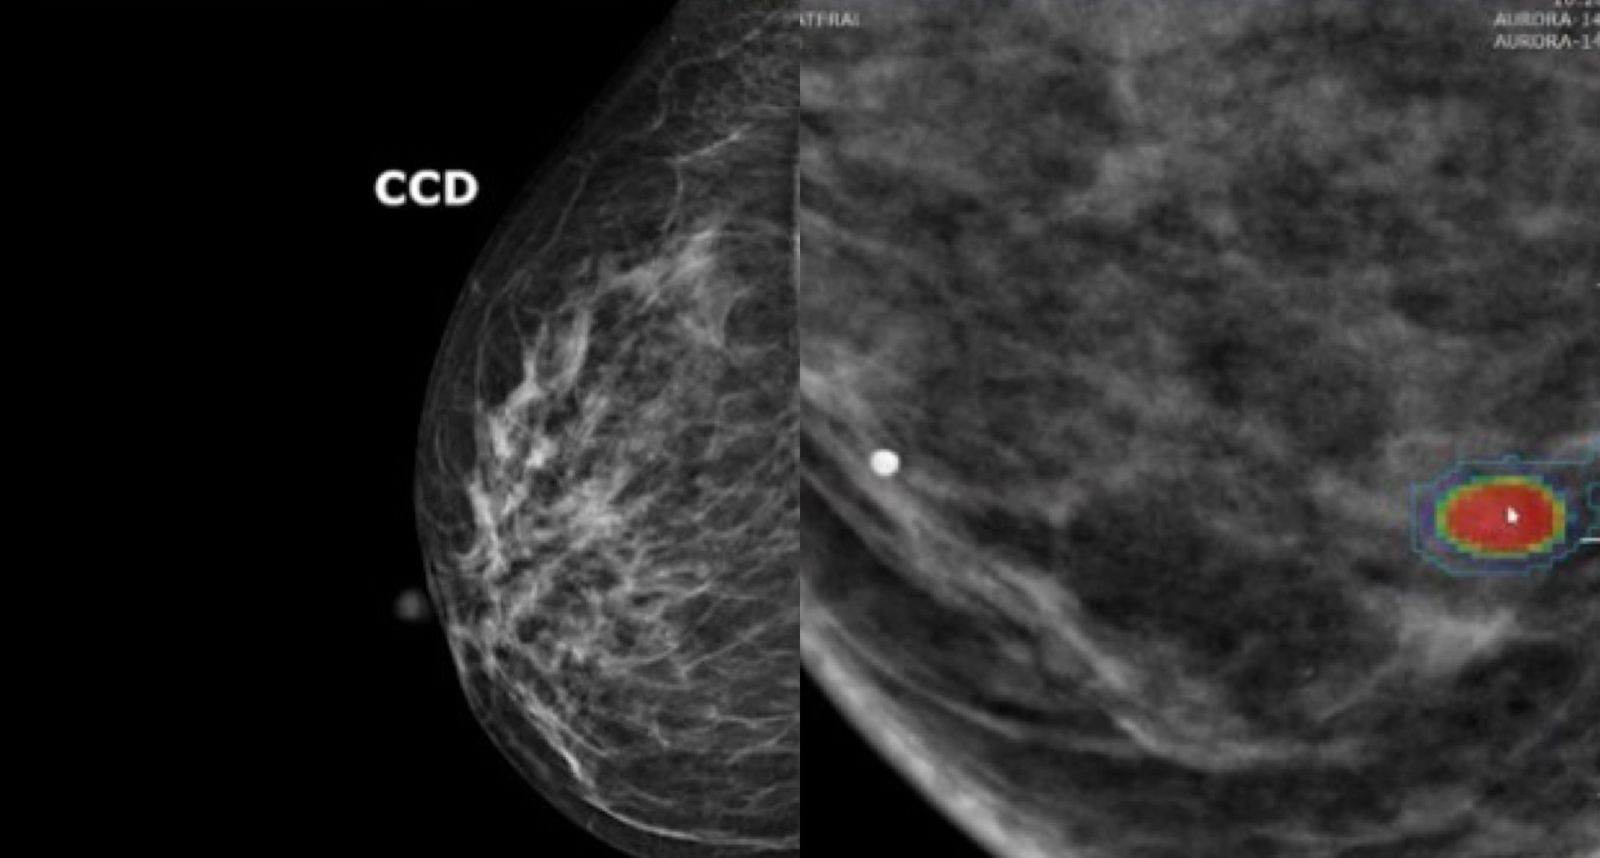

A ferramenta de IA analisa os laudos das mamografias, identificando nódulos e sinais de alerta com agilidade. O sistema consegue reconhecer padrões nas imagens que podem indicar lesões ou microcalcificações suspeitas. Paula Castilho, especialista em tecnologia de medicina diagnóstica, afirma que a IA permite priorizar exames com maior risco, agilizando a avaliação de possíveis problemas.